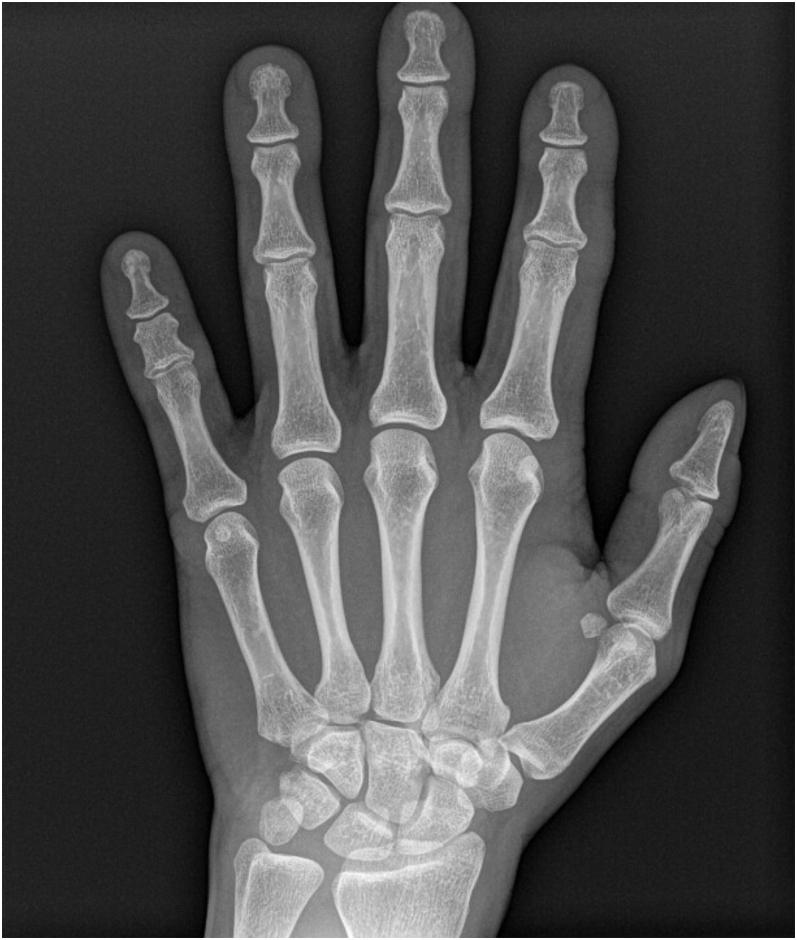

腕管综合征的手术减压通常是成功的,而失败是罕见的。持续性或复发性腕管综合征的诊断是基于彻底的记忆和临床检查,明确潜在的合并症,神经传导研究,并区分复发、持续或新发主诉。腕管释放失败的治疗可能需要翻修手术,包括腕横韧带的重新释放、外神经松解术和皮瓣。下鱼际脂肪垫皮瓣或其他局部、区域或远端皮瓣可用于重做腕管松解。目前,缺乏令人信服的证据证明附加皮瓣手术的优越性。术后护理正朝着早期运动而不是固定运动的方向发展,通过神经滑动练习来防止粘连并促进神经恢复。虚拟现实最近被添加到术后方案选择中。

Surgical decompression of carpal tunnel syndrome is usually successful, and failure is rare. Diagnosis of persistent or recurrent carpal tunnel syndrome is based on thorough anamnesis and clinical examination, defining underlying comorbidities, nerve conduction studies and distinguish recurrent, persistent or new complaints. Management of failed carpal tunnel release may require revision surgery, which includes redo release of the transversal carpal ligament, external neurolysis and flaps. A hypothenar fat pad flap or other local, regional or distant flaps may be added to a redo release of the carpal tunnel. Currently, convincing evidence to superiority of additional flap surgery is lacking. Postoperative care is evolving toward early motion rather than immobilization, with nerve gliding exercises to prevent adhesions and promote nerve recovery. Virtual reality was recently added to postoperative protocol options.